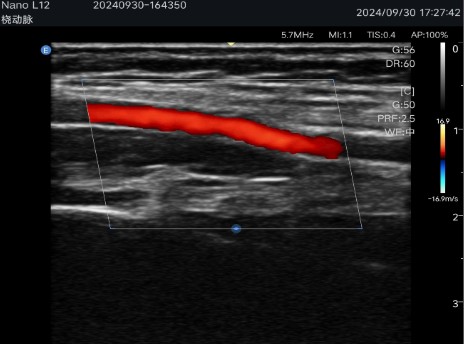

Available with linear probe Linear - high frequency, lower penetration, high resolution (ideal for superficial structures and fine details such as vessels, thyroid, breast, testicle, etc.).

Multiple imaging modes: Includes B-mode, C-mode, M-mode and Pulsed Doppler (PW), ensuring precise visualizations for various clinical applications.